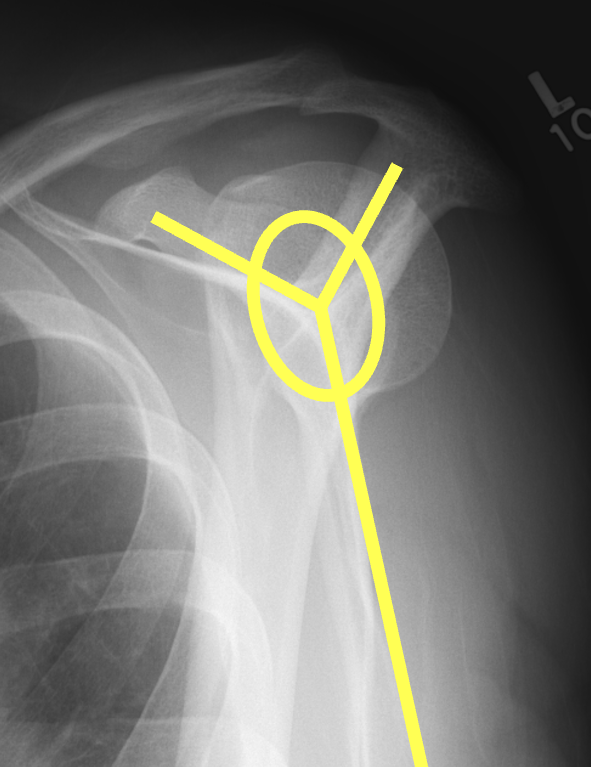

Scapular lateral

Center of the humeral head must be centered on the Y / Mercedes sign

Y is formed by

- coracoid anteriorly

- scapular spine posteriorly

- scapula body inferiorly

Posterior shoulder dislocation